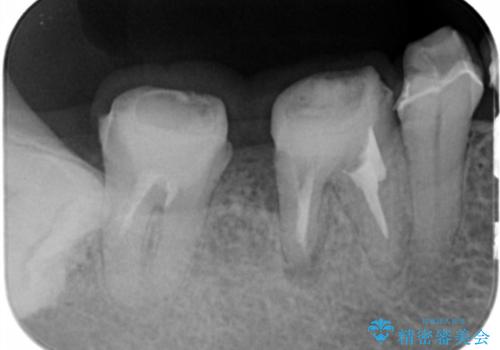

治療前にX線写真や歯周病検査を行ったところ、中等度に進行した歯周病が見つかりました。

抜歯も検討されるような骨の形態ではありますが、歯周病により溶けてしまった骨を再生させる歯周病再生治療を行うこととしました。